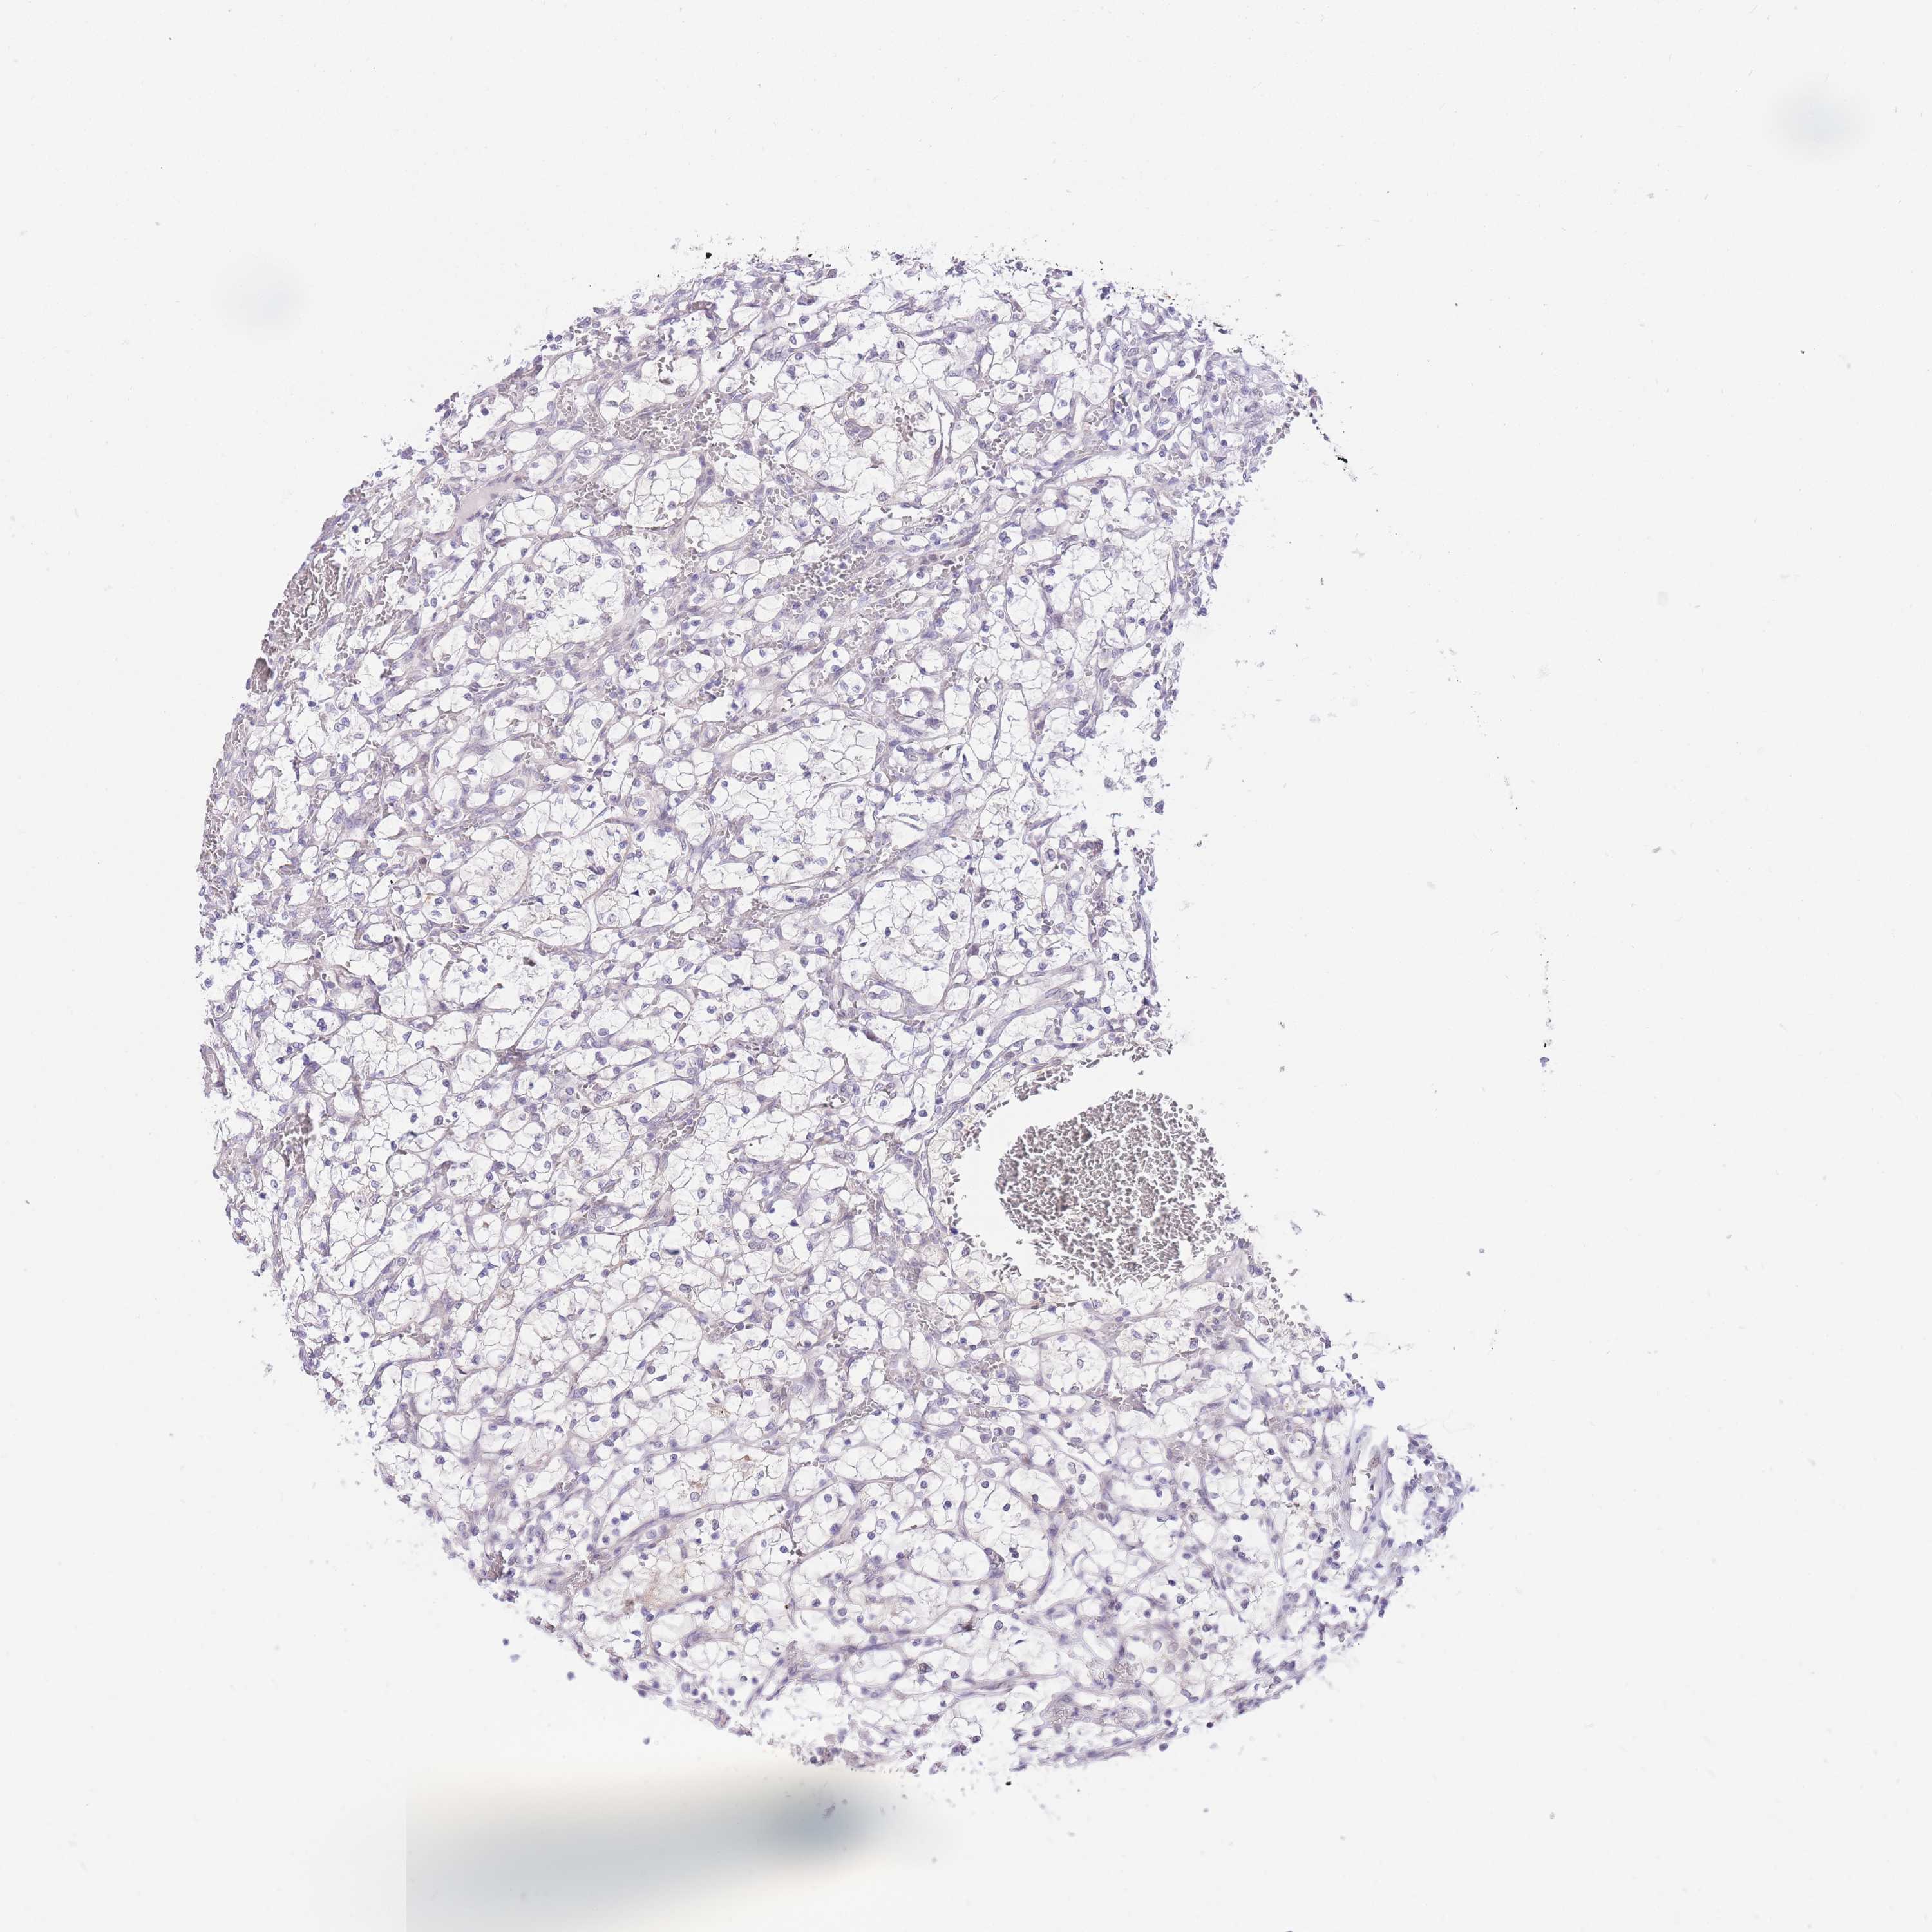

KIDNEY RENAL PAPILLARY CELL CARCINOMA (TCGA) - Interactive survival scatter ploti

The Survival Scatter plot shows the clinical status (i.e. dead or alive) for all individuals in the patient cohort, based on the same data that underlies the corresponding Kaplan-Meier plots. Patients that are alive at last time for follow-up are shown in blue and patients who have died during the study are shown in red.

& Survival analysisi

Kaplan-Meier plots summarize results from analysis of correlation between mRNA expression level and patient survival. Patients were divided based on level of expression into one of the two groups "low" (under cut off) or "high" (over cut off). X-axis shows time for survival (years) and y-axis shows the probability of survival, where 1.0 corresponds to 100 percent.

UBXN7 is not prognostic in Kidney Renal Papillary Cell Carcinoma (TCGA)

Best expression cut offi

Based on the FPKM value of each gene, patients were classified into two groups and association between prognosis (survival) and gene expression (FPKM) was examined. The best expression cut-off refers the FPKM value that yields maximal difference with regard to survival between the two groups at the lowest log-rank P-value. Best expression cut-off was selected based on survival analysis .